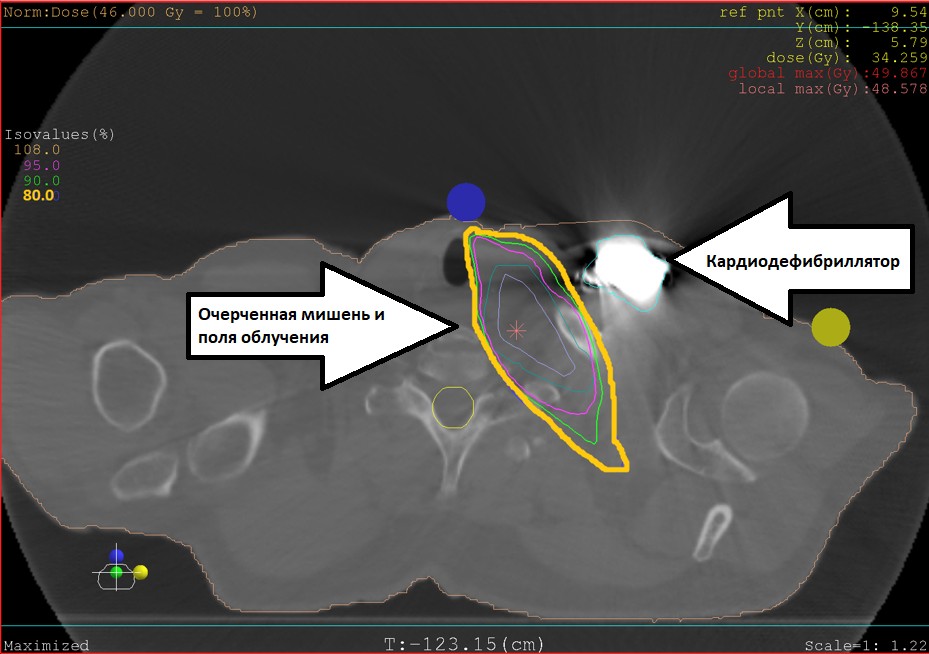

Была показана безотлагательная лучевая терапия. Но региональные коллеги посчитали облучение рискованным и невозможным из-за сопутствующей сердечной патологии (уже длительное время мужчина страдает ишемической болезнью сердца, а с 2016 года - жизнеугрожающей желудочковой тахикардией, для борьбы с которой ему был имплантирован кардиовертер-дефибриллятор). Опасность лечения была связана как с лучевой нагрузкой на область сердца, так и с помехой, которую оно создавало работе имплантированного устройства. Отключение кардиодефибриллятора могло стоить жизни.

Медицинские физики Центра очень точно рассчитали план лечения и распределили поля облучения так, чтобы максимально обойти кардиодефибриллятор и при этом эффективно воздействовать на опухоль. Врачи-аритмологи постоянно вели мониторинг работы кардиодефибриллятора, кардиологи курировали больного в течение всего курса.